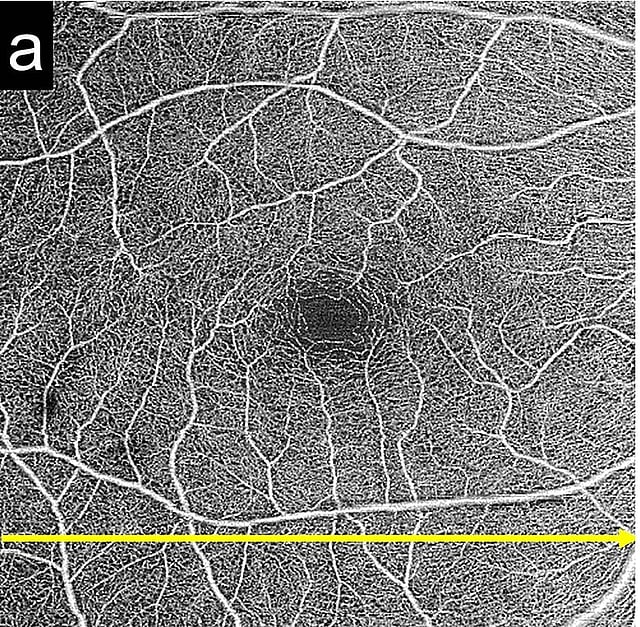

Pachyvessels are pathologically dilated large choroidal vessels and are associated with the pathogenesis of several pachychoroid-related disorders, including central serous chorioretinopathy. We aimed to investigate the prevalence of and risk factors for pachyvessels in the Japanese population. We included 316 participants (aged ≥ 40 years) with normal right eyes. The presence of pachyvessels (vertical diameter > 300 µm, distance to the retinal pigment epithelium < 50 µm) was determined using 6 × 6 mm macular swept-source optical coherence tomography images, and associated risk factors were investigated. Subfoveal choroidal thickness was measured, and its associated risk factors investigated. The overall prevalence of pachychoroids was 9.5%. Regression analysis showed that a younger age, shorter axial length, male sex, and smoking were significantly associated with the presence of pachyvessels (p = 0.047; odds ratio [OR] 0.96 per year, p = 0.021; OR 0.61 per 1 mm, p = 0.012; OR 3.08 vs. female, and p = 0.011; OR 3.15 vs. non-smoker, respectively) and greater choroidal thickness (p < 0.001, p < 0.001, p < 0.003, and p < 0.017, respectively). The results were consistent with other research findings which showed that pachychoroid-related disorders such as central serous chorioretinopathy were associated with younger age, male sex, shorter axial length, and smoking. Smoking may be associated with choroidal circulatory disturbance in the Japanese population.

Pachyvessels are large, inwardly displaced, pathologically dilated choroidal vessels. Pachyvessels can cause focal choriocapillaris thinning and are associated with the pathogenesis of central serous chorioretinopathy (CSC)1. In optical coherence tomography (OCT) angiography images of CSC eyes, the area of choriocapillaris flow void was found to be high2, and the location of the choriocapillaris flow void was associated with the distribution of the underlying choroidal vessels3,4. Studies suggest that pachyvessels impair choriocapillaris and may be responsible for retinal pigment epithelium (RPE) damage, resulting in CSC. Therefore, pachyvessels may be a preclinical sign of CSC, and normal eyes with pachyvessels may have a potential risk of CSC.

Baek et al. reported that the prevalence of pachyvessels was 25%, 46%, 85%, 96%, and 100% in non-neovascular age-related macular degeneration (AMD), neovascular AMD, thin choroid polypoidal choroidal vasculopathy (PCV), thick choroid PCV, and CSC eyes, respectively5. However, the prevalence of pachyvessels in the normal healthy population without degenerative disease has not been studied. Thus, investigation of pachyvessel prevalence will increase understanding of its pathogenesis in CSC, PCV, and AMD. Therefore, our study evaluated the prevalence of pachyvessels and associated risk factors in a normal Japanese population. In addition, the risk factors associated with increased subfoveal choroidal thickness were studied.